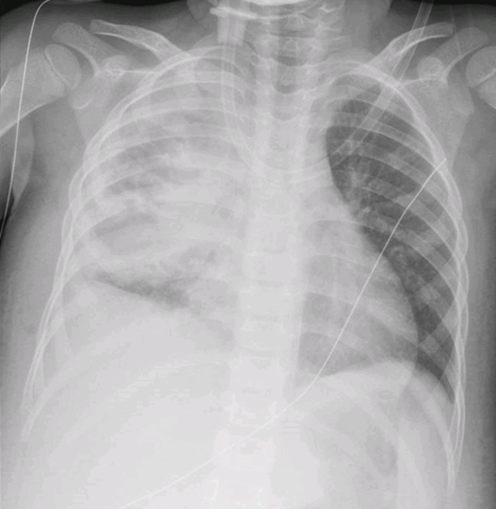

A 6-week-old male infant was brought to the emergency department with a three-day history of irritability, decreased food intake and a polymorphic skin eruption. He had no significant medical history, was exclusively breastfed with good weight gain. None of his family members had similar symptoms or lesions. The infant was in good general condition. Skin examination revealed an erythematous base with scattered vesicles, pustules and papules. The lesions were more prominent on the scalp, back and abdomen, including the neck, inguinal and axillary regions (Figure 1). Blood parameters were within reference ranges for age, with no increased inflammatory markers. Nevertheless, due to the exuberance of the lesions, a bacterial infection was suspected and intravenous flucloxacillin was initiated.

Figure 1A and 1B. Lesions in the torso: scattered vesicles, pustules, papules and nodules in an erythematous base.